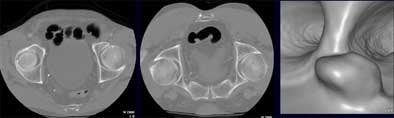

![]() |

| Axial image (left) shows partial collapse in sigmoid colon in supine acquisition. Scanning the patient in prone position (middle) revealed a polyp, shown in reconstructed 3D view (right). Images courtesy of Dr. Noga Rogalla and Dr. Patrick Hein. |